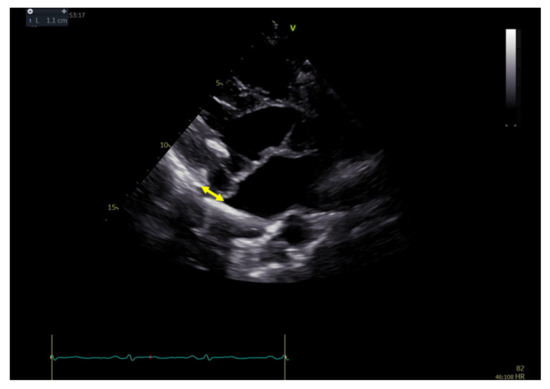

2.3. Echocardiography

- Carmo, P.; Andrade, M.J.; Aguiar, C.; Rodrigues, R.; Gouveia, R.; Silva, J.A. Mitral annular disjunction in myxomatous mitral valve disease: A relevant abnormality recognizable by transthoracic echocardiography. Cardiovasc. Ultrasound 2010, 8, 53. [Google Scholar] [CrossRef] [PubMed]

- Eriksson, M.J.; Bitkover, C.Y.; Omran, A.S.; David, T.E.; Ivanov, J.; Ali, M.J.; Woo, A.; Siu, S.; Rakowski, H. Mitral annular disjunction in advanced myxomatous mitral valve disease: Echocardiographic detection and surgical correction. J. Am. Soc. Echocardiogr. 2005, 18, 1014–1022. [Google Scholar] [CrossRef] [PubMed]